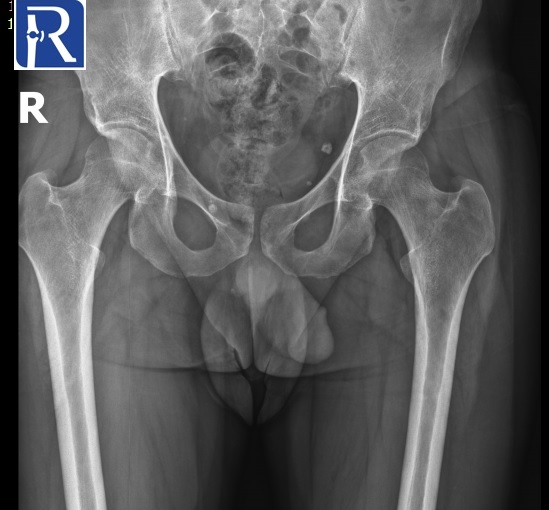

Image Details: AP X-Ray shows the diffuse decrease in density of left proximal femur, suggesting the osteopenia of left proximal femur. MR images shows the edema like signal changes in neck and head of left femur. Mild amount of effusion is present in left joint. Radiological (bone marrow edema and osteopenia of proximal femur) and clinical (young adult male with unilateral hip pain) suggest the diagnosis of transient osteoporosis of hip.

X-rays are normal initially but usually abnormal by 4-8 weeks following the onset of symptoms.

X-rays may show a loss of bone density as in our case.